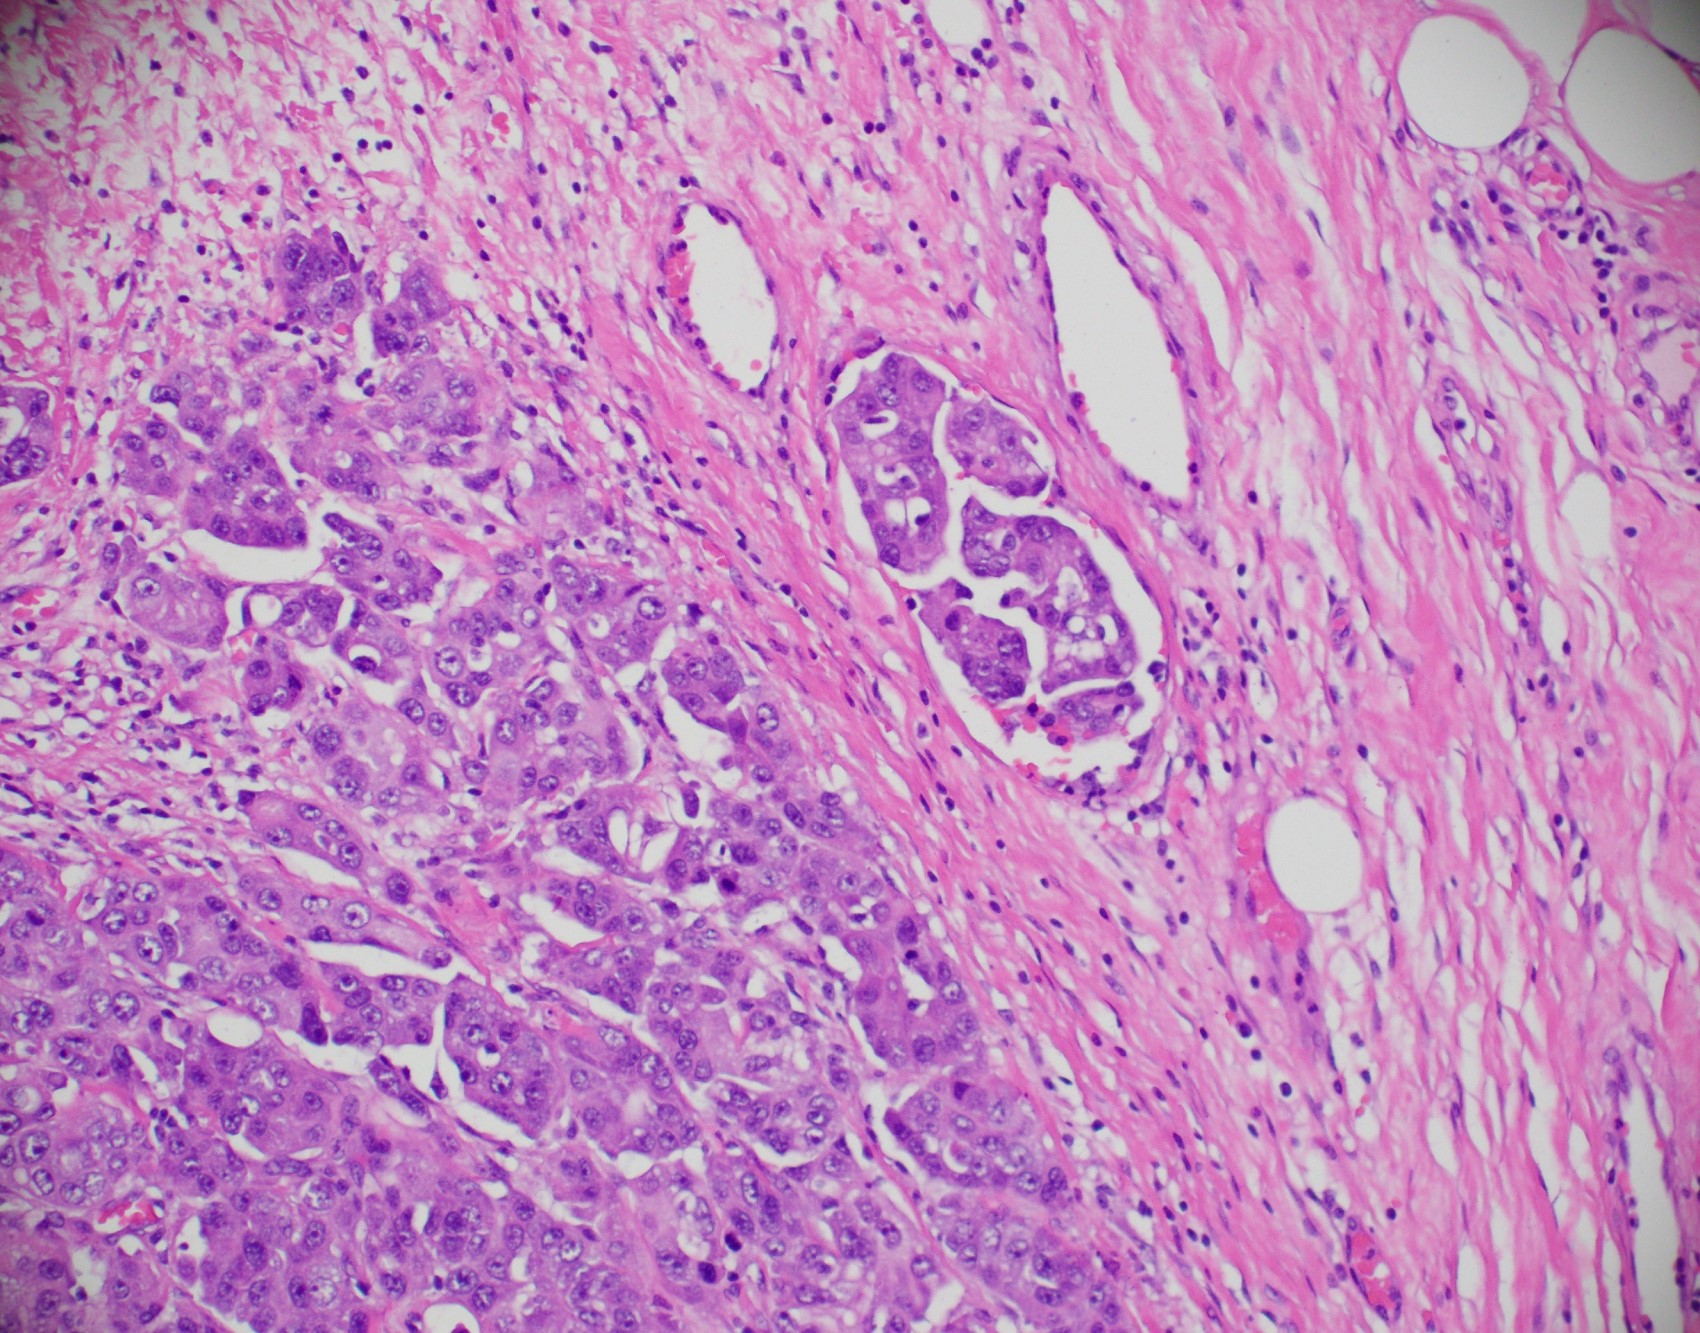

Microscopic (histologic) description

- Histological features of IBC NST vary considerably from case to case and even within the same case

- Margins vary from highly infiltrative, permeating the surrounding tissue, to continuous pushing margins

- Architecture varies from sheets, nests, clusters, cords or individual cells (but lacks the cytomorphological characteristics of invasive lobular carcinoma)

- Tubular formations are prominent in well differentiated tumors but absent in poorly differentiated tumors

- 2 distinct growth patterns exist:

- Large and solid nests or syncytial infiltrative growth pattern with little associated stroma and an expansive growth that compresses the surrounding stroma (e.g., most basal-like breast cancers)

- Tumors characterized by small cancer nests accompanied by marked fibrosis (desmoplastic / scirrhous); this type diffusely infiltrates the surrounding tissue as an irregular shaped spiculated mass

- Calcification in 60% of cases, variable necrosis

- Elastosis involves stroma, wall of vessels and ducts and causes grossly noted chalky streaks

- Often ductal carcinoma in situ (DCIS) (up to 80%)

- In some cases, DCIS is extensive

- Associated DCIS is usually of same nuclear grade as the invasive carcinoma

- Perineural invasion (28%)

- No myoepithelial cell lining (as seen in DCIS or benign lesions)

- Angiolymphatic invasion in 35%; differs from tissue retraction because:

- Occurs outside margin of carcinoma

- Does not conform precisely to space it is in

- Endothelial lining is present and is CD31+, ERG, D2-40+, CD34+ and factor VIII+

Microscopic (histologic) images

Contributed by Julie M. Jorns, M.D., Kristen E. Muller, D.O., Gary Tozbikian, M.D. and Emad Rakha, M.D.